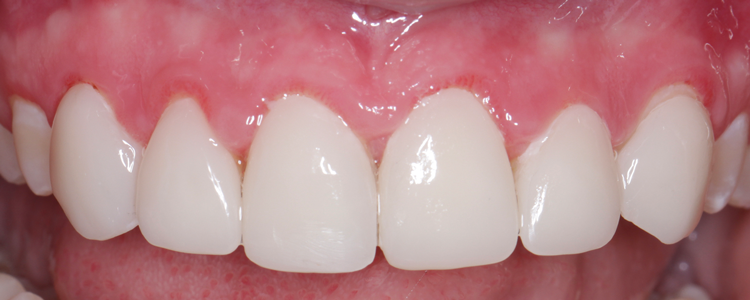

(6.) Posttreatment retracted close-up view of the composite veneers after they were placed with a self-adhesive resin cement.

Figure 6